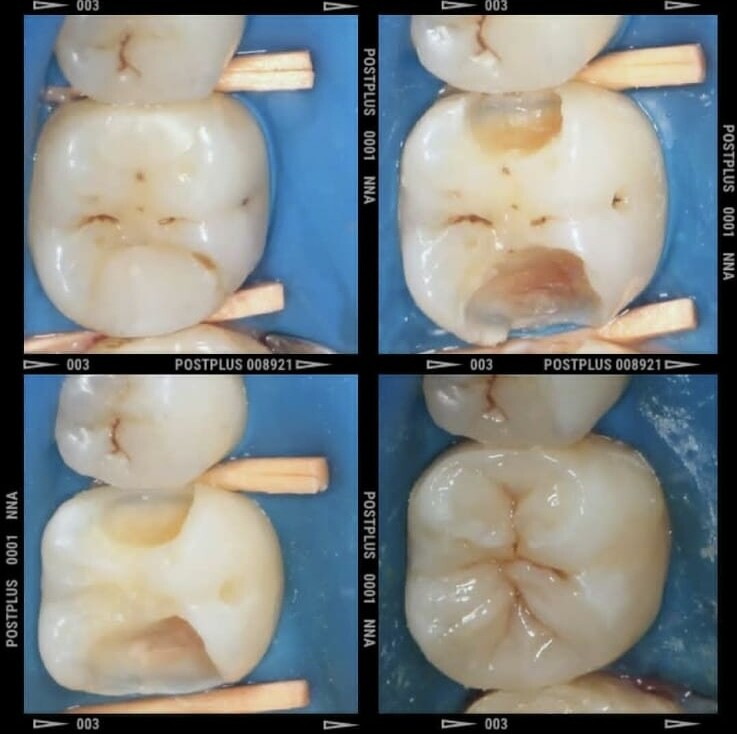

Лечение зубов

Лечение кариеса

Пломбирование зубов

Лечение пульпита